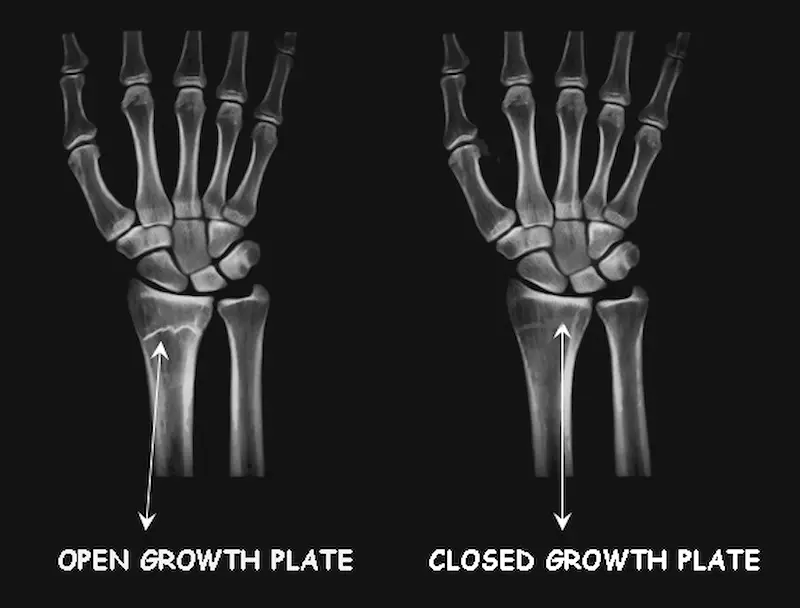

How to check if Growth Plates are still open.

Growth plate status cannot be determined at home.

X-ray scans must be performed by a medical professional in a clinical setting to accurately assess skeletal maturity.

What the Doctor Does

A doctor (typically a pediatric endocrinologist) will look for a visible gap at the ends of the bones.

A visible line means the plate is open; a solid bone connection means it has fused.

X – ray showing Open and Closed plates.

The Greulich-Pyle Method

The standard tool used by physicians is the Greulich-Pyle Atlas.

A doctor compares an X-ray of your left hand and wrist against this established atlas of maturity markers. This allows them to determine whether your skeleton is maturing faster or slower than your chronological age, a concept known as bone age.

Again, X-ray scans must be performed by a medical professional in a clinical setting to accurately assess skeletal maturity not at home.